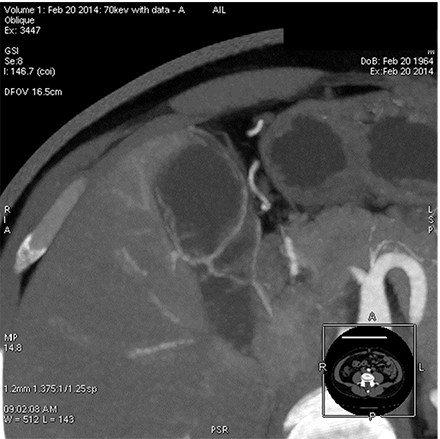

能谱 低keV图像血管成像

胆囊供血动脉   50keV

胆囊动脉及其分支发育细小,常规CTA难以完整显示,即使提高造影剂浓度、总量及注射流率也无法来满微小动脉显示的需求,受扫描时相影响较大。

GSI扫描能使用低keV 图像满足空间分辨率和密度分辨率兼顾的要求,在常规造影剂注射方案情况下,一次扫描通过调整keV同时满足诊断及微小动脉显示需要。该方法可在临床解剖研究、病变血供发现、血管受侵状况、手术指导等方面有重要作用。